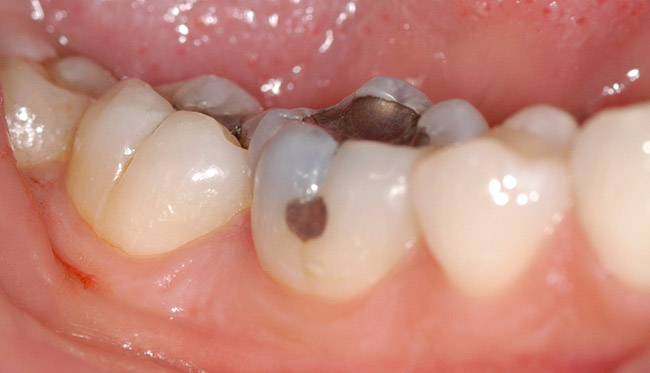

When all caries has been removed, the cavity preparation should be rinsed with the air/water syringe for 10 seconds and dried. Using a 32% to 37% phosphoric acid gel, the dentin portions of the cavity preparation should be etched for no more than 5 seconds to “cleanse” the surface of the dentin. An air/water syringe is used for 15 seconds to neutralize and remove any remaining etch material.27 The exposed dentin areas of the preparation are then carefully moistened using a cavity desensitizer such as Gluma® (Heraeus Kulzer) a formula of 5% glutaraldehyde and 35% HEMA (hydroxylethyl methacrylate) in water. The Gluma is placed using a small, disposable, flocked tip applicator.28 The dentin is left slightly moist, and is then based out using glass-ionomer cement (Figure 2). Glass-ionomer cement has superior biocompatibility. Glass ionomer has a similar coefficient of thermal expansion to dentin and it supplies fluoride to help remineralize any surrounding tooth structure it may contact. Glass-ionomer cements remain dimensionally unchanged during their polymerization process and, therefore, do not place any stress on the fluids of the dentinal tubules.29

Figure 2  Shows a view of the tooth isolated by the rubber dam. The preparation is complete and the tooth has been total etched for 5 seconds and thoroughly rinsed with water for 15 seconds. The tooth has been blotted dry and a flowable base is being bulk-filled into the deepest portions of the cavity preparation.

Figure 2